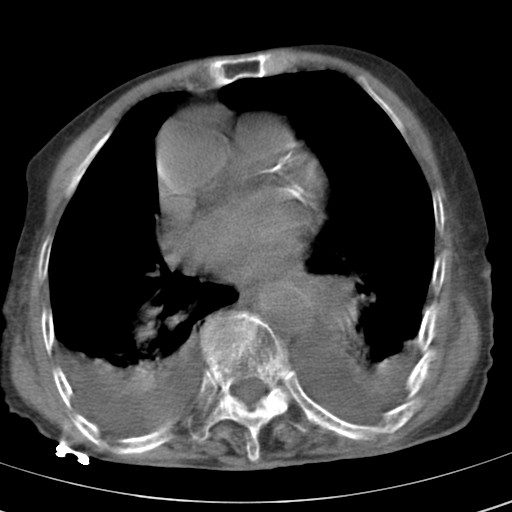

女,93岁,摔伤后检查。

右肺炎症,心功能不全伴双侧胸腔积液,右下肺膨胀不全,食管裂孔疝,冠脉钙化,心包少量积液,左侧肋骨骨折,请上传骨窗.

右侧锁骨\\肩胛骨骨折、右侧湿肺,心功能不全伴双侧胸腔积液,右下肺膨胀不全,左膈破裂或食管裂孔疝,冠脉钙化,心包少量积液,请上传骨窗.

右肺炎症,心功能不全伴双侧胸腔积液,右下肺膨胀不全,食管裂孔疝,冠脉钙化,心包少量积液,左侧肋骨骨折,右肩甲骨粉碎性骨折。93岁,高寿哇!

右肺炎症,心功能不全伴双侧胸腔积液,右下肺膨胀不全,食管裂孔疝,冠脉钙化,心包少量积液,左侧肋骨骨折,右肩甲骨粉碎性骨折。